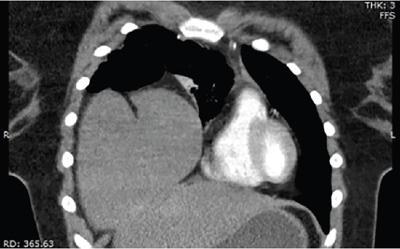

Shrinivas B. Desai, Ritu K. Kashikar, Shreya Shukla Radiological signs are classical and distinctive abnormalities characteristic of a disease. These can be seen on any imaging modality. Resemblance to commonly seen objects and patterns form the basis of radiological signs. The aim is to help the reader associate, understand and memorize these pathologies with the aid of signs. Various signs pertinent to hepatobiliary system are described in the chapter. Described on MRI when liver lesion shows a peripheral rim of high T2 signal intensity with the centre of the lesion appearing isointense to the background of noncirrhotic liver on T2WI mimicking an atoll. It is considered a characteristic sign of an inflammatory hepatic adenoma (image) but is only seen in about one-third of cases Extrinsic smooth impression over medial aspect of duodenum along its posteroinferior aspect, seen in pancreatic head pathologies like carcinoma. This sign is seen in pancreatic adenocarcinoma Presence of a persistently hyperattenuating dot within a lesion on arterial and portal venous CT. This corresponds with peripheral nodular enhancement seen on dynamic MR. Presence of bright dot suggests that the lesion is a hemangioma and helps in ruling out metastasis Ultrasound appearance of multiple cystic spaces or lesions that has been used to describe the appearance of an intraductal papillary mucinous neoplasm of the pancreas. Seen on contrast CT in portal hypertension. The appearance is based on resemblance to Medusa from Greek mythology. Dilated engorged paraumbilical veins radiating across umbilicus to join systemic veins is seen. This sign is seen in Caroli’s disease on contrast CT. Enhancing dots within dilated intrahepatic bile ducts represent portal radicles. Caroli’s disease Irregularly dilated pancreatic duct with multiple strictures and intervening dilatation with associated dilated side ductules resemble multiple lakes supplied by a single territory. Best seen in MRCP images. Chronic pancreatitis It is a finding on MRI and CT and is best seen on MRI T2-weighted and postcontrast T1-weighted sequences. Small necrotic/purulent areas in the pyogenic abscess ‘cluster’ together and then coalesce into a larger necrotic/purulent areas, eventually becoming a larger septated abscess cavity. At the periphery of these clusters: Associated with pyogenic hepatic abscesses and can help differentiate pyogenic abscesses from other types of liver lesions Abrupt termination of gas within the proximal colon at the level of radiological splenic flexure. The inflammatory exudates in pancreatitis extend to the phrenicocolic ligament giving rise to this sign Seen on grey scale ultrasound as a reverberation artifact when small calcific or highly reflective objects are imaged. The colour comet-tail artifact is an ultrasonographic sign seen in a number of situations when colour Doppler scanning is performed. This sign occurs in cases of traumatic right-sided diaphragmatic rupture with resultant partial herniation of liver through the defect. Separation of the herniated liver from its intra-abdominal component is via a small constriction at the level of diaphragm resembling a cottage loaf. Cottage loaf is a particular shape of bread in which larger and smaller roughly spherical balls are squashed together. Traumatic right-sided diaphragmatic rupture with resultant partial herniation of liver Bile eccentrically outlines luminal stone, creating a low attenuation crescent. Best seen on MRCP images. Choledocholithiasis Dilatation of both pancreatic duct and CBD is referred to as the double duct sign. Positive double duct sign suggests the diagnosis of carcinoma of the head of the pancreas and ampullary tumours and is hence considered ominous. Occasionally the sign may be seen in impacted gallstone in the distal duct. This feature is seen in patients with liver abscess on contrast-enhanced CT. A double, inner hyperattenuating and outer hypoattenuating rim is seen surrounding the hypodense abscess. The inner hyperattenuating rim corresponds to the enhancing abscess membrane, while the outer rim corresponds to the edema of the surrounding liver which appears hypodense and may show delayed enhancement. Liver abscess A positive duct penetrating sign is when a mass is penetrated by an unobstructed pancreatic duct; this makes focal pancreatitis the most likely cause rather than pancreatic carcinoma. This sign is best appreciated on MRCP (or ERCP). A radiographic sign that can be useful in differentiating between focal pancreatitis (inflammatory pancreatic mass) from pancreatic carcinoma. The duct-penetrating sign on MRCP is more helpful in differentiating between these two entities than a delayed enhancement pattern on CT or MRI It occurs when there is both limy bile and a gallstone in the common bile duct. The linear vertical radiopaque bile forms the line of the exclamation mark (i.e. !), whilst a more distal calculus forms the ‘dot’ at the end of the exclamation mark. Pathognomonic imaging sign of the rare diagnosis of limy bile on plain abdominal radiography Nonenhancing ruptured lesion with peripheral rim enhancement showing discontinuity from the rest of the liver and protruding from the liver surface is called the enucleation sign. Ruptured HCC Enlargement of the pericholecystic space. One of the signs of liver cirrhosis Can be seen on technetium 99m sulphur colloid scans of the liver and spleen, as well as CT studies. It occurs as a focal area of increased radiopharmaceutical uptake in the medial segment of the left hepatic lobe (segment IV) occurring as a result of SVC obstruction and portosystemic venous shunting between the superior vena cava and the left portal vein via the internal thoracic and paraumbilical veins. The equivalent of this sign may also be seen on contrast-enhanced CT scans as a hypervascular region. Budd–Chiari syndrome causes the hot spot sign in the caudate lobe